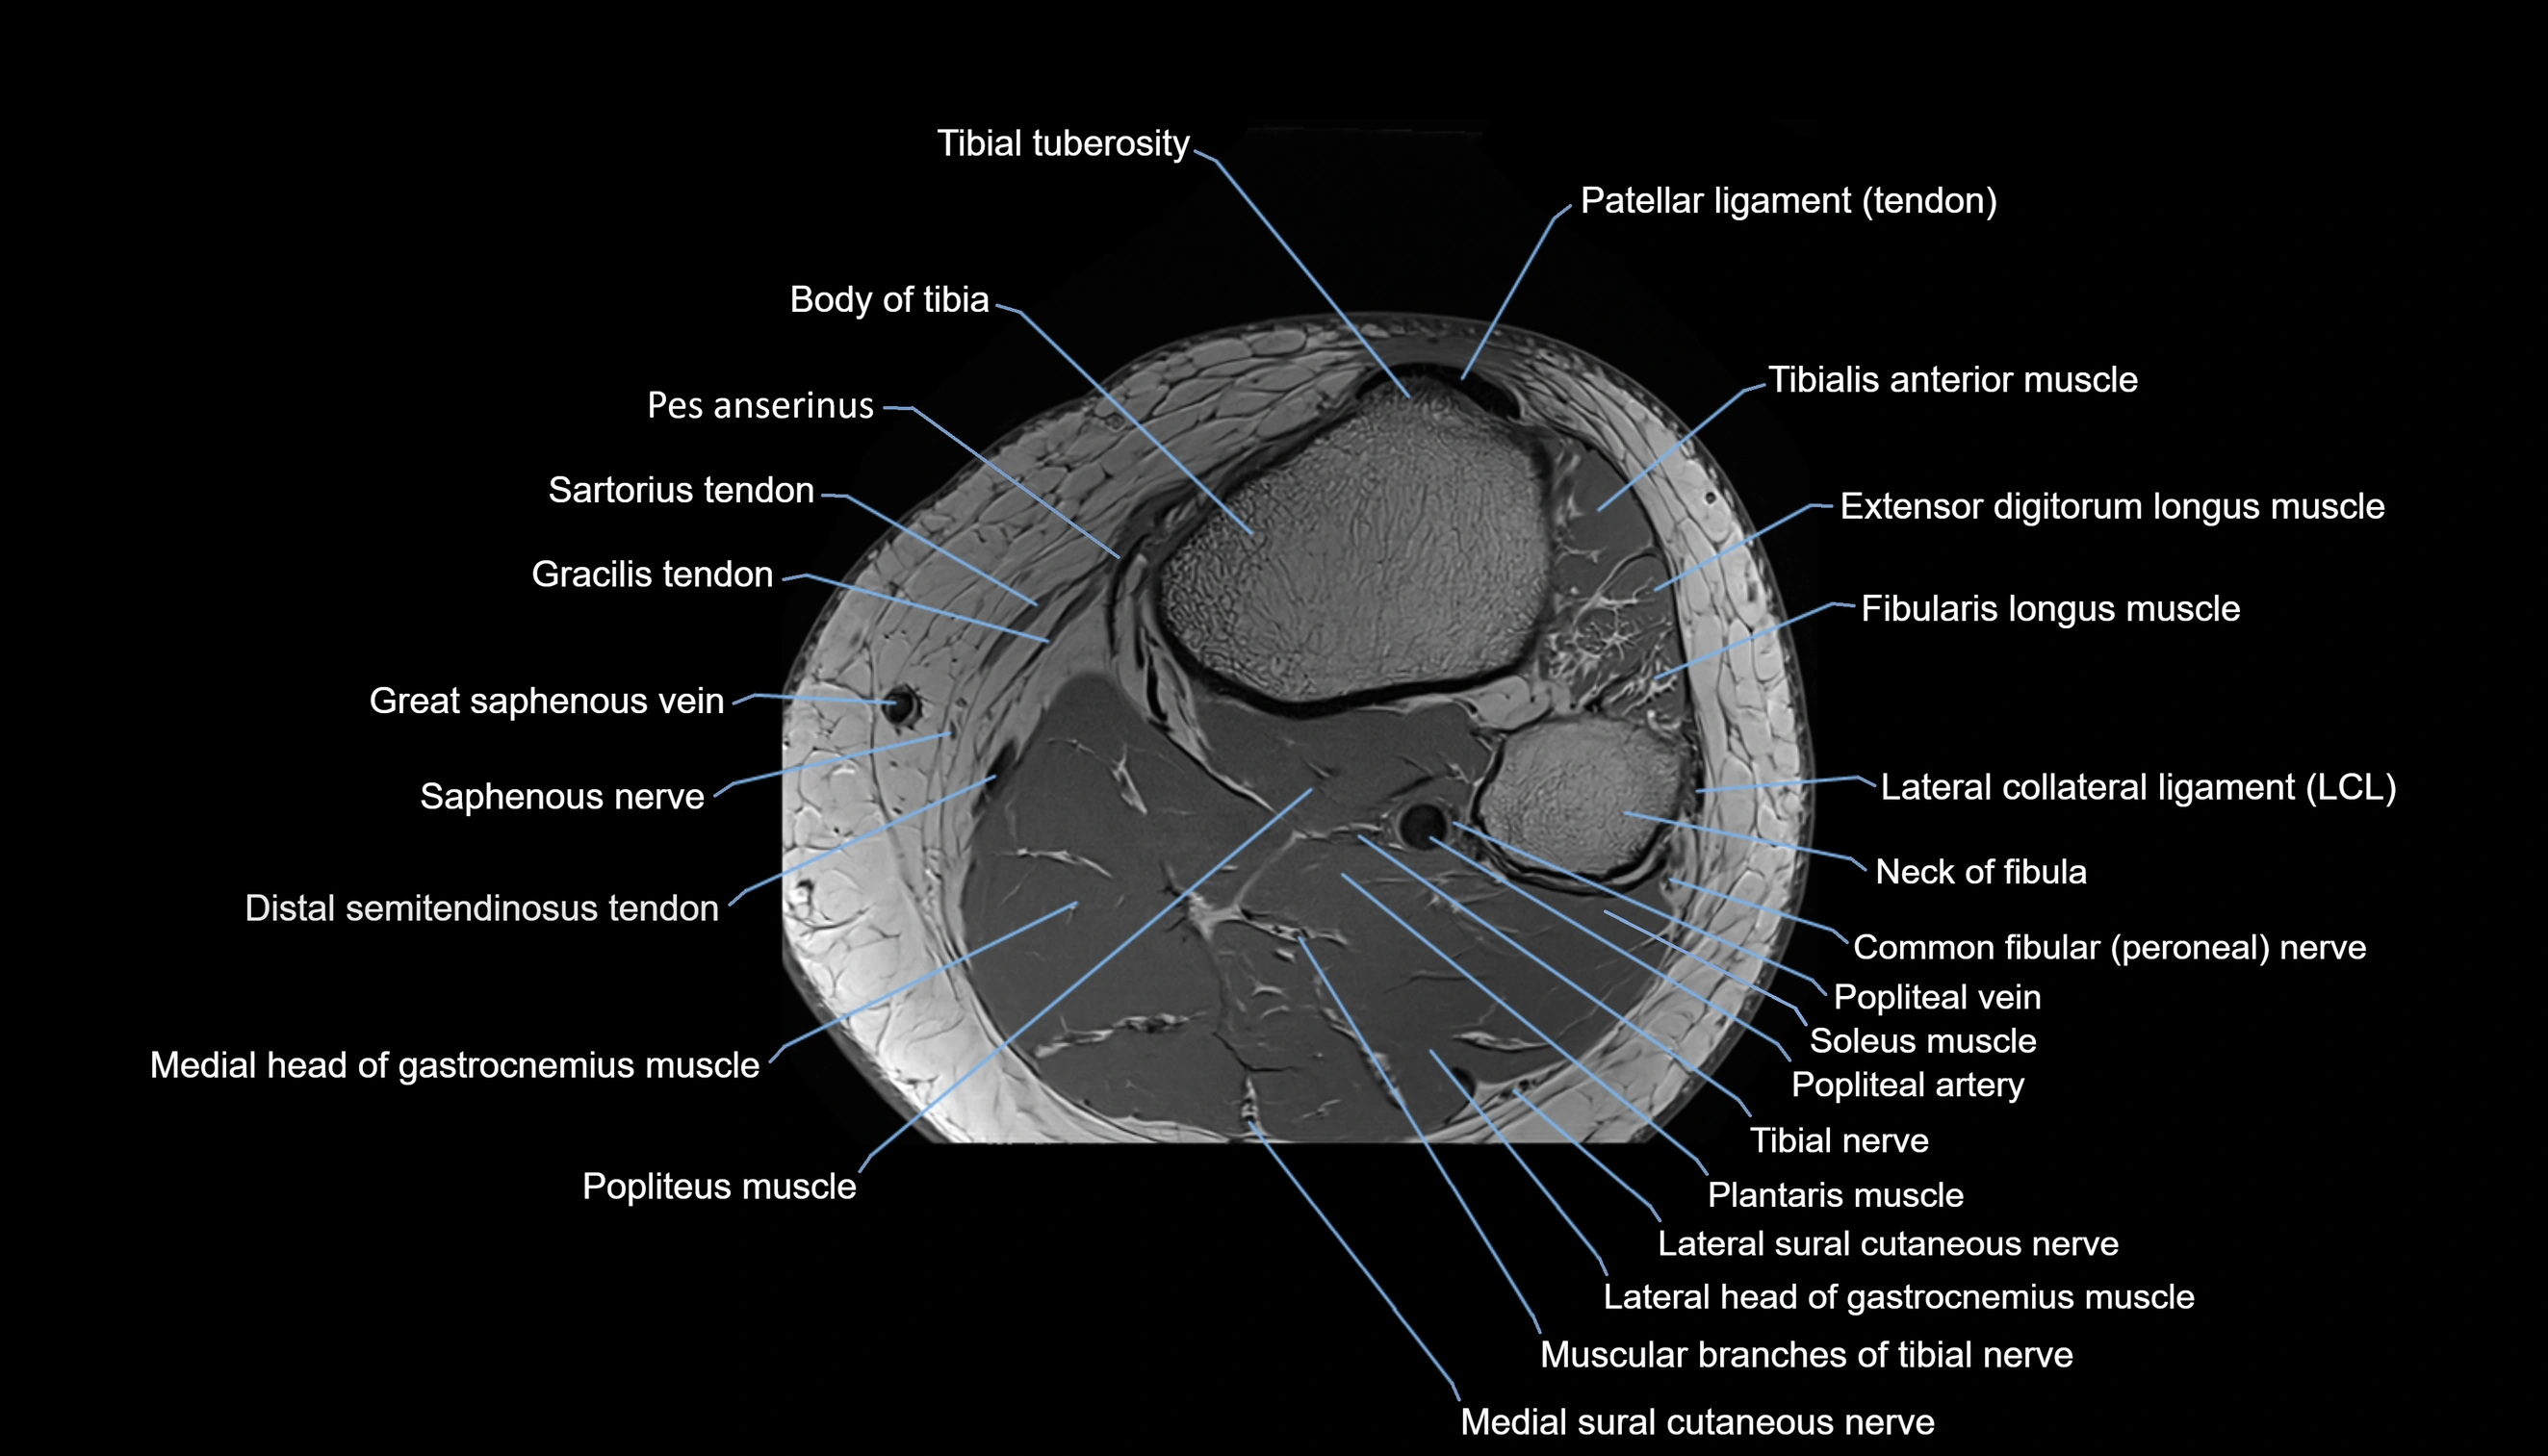

- Body of tibia

- Common fibular nerve

- Extensor digitorum longus muscle

- Fibularis longus muscle (peroneus longus muscle)

- Gracilis tendon (Distal)

- Head of fibula

- Lateral collateral ligament

- Lateral sural cutaneous nerve

- Medial head of gastrocnemius muscle

- Medial sural cutaneous nerve

- Muscular branches of tibial nerve

- Neck of fibula

- Patellar tendon (patellar ligament)

- Plantaris muscle

- Popliteal artery

- Popliteal vein

- Popliteus muscle

- Saphenous nerve

- Sartorius tendon (Distal)

- Soleus muscle

- Tibial nerve

- Tibial tuberosity

- Tibialis anterior muscle